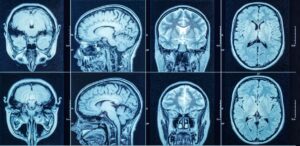

By Dr. Petrus Raulino What is Schizophrenia? Schizophrenia is a chronic and potentially disabling psychiatric disorder that can affect the ability to think, feel